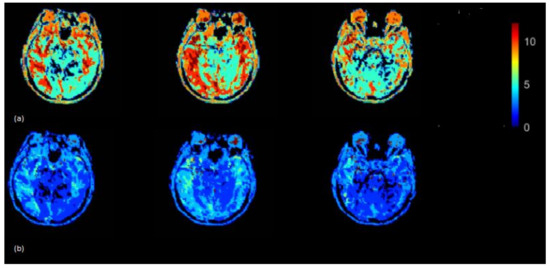

The Tmax (seconds) map was generated using the rescaled AIF (VOF approach) (Figure 6) (top) and non-rescaled AIF (Figure 6) (bottom). The Tmax map generated using the rescaled AIF showed increased values in the axial brain slices in the left and right hemispheres. The mean Tmax values (range of 0–12 s) based on 15 subjects using non-rescaled (AIF ROI width = 5 voxels) and VOF approach were 4 s and 7 s, respectively. The derivation of Tmax is performed from the residue function (R(t)), which is achieved by deconvolution of Equation (6). Tmax is the argument, i.e., ‘t’ of the maximum of R(t). The deconvolution utilizes a matrix method called the circulant singular deconvolution, which is sensitive to the peak amplitudes of AIF (cSVD) [23]. The changed AIF amplitude used in the cSVD algorithm shifts the maximum of R(t) to a higher time points ‘t’ which accounts for higher Tmax values. The change in Tmax is consistent with a previous study where different AIFs with changed amplitudes and similar shape selected by different algorithms resulted in change of Tmax values [1]. The increased Tmax maps generated by the rescaled AIF may allow clinicals to visualize the critically hypoperfused regions which are likely to be salvageable.

Figure 6.

Tmax (seconds) map generated by using rescaled AIF (a) and non-rescaled AIF (b) for one subject. Tmax map generated using rescaled AIF represents increased values in the shown axial brain slices.